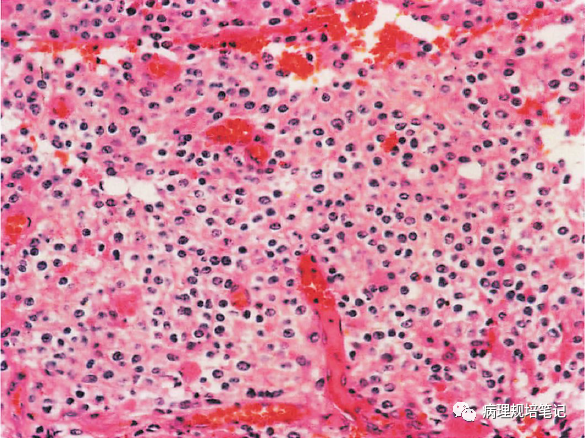

图9-1 少突胶质细胞瘤

瘤细胞密度中等,大小一致,透亮(蜂窝状),见致密的分支状毛细血管网